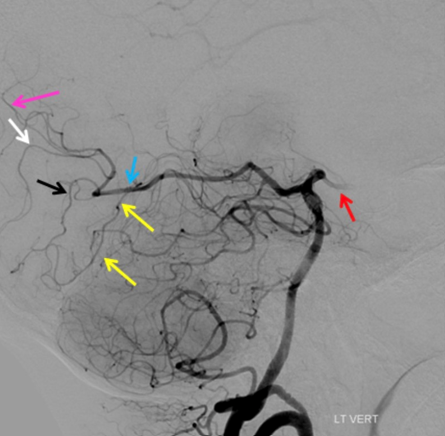

Can you name the branch marked by the black arrow? It is a paramedian branch that sits just above the tentorium. Be sure to comment your answer and check back on Thursday!

#neurotwitter #neuroanatomy #endovascular @esmintsociety @cvsection